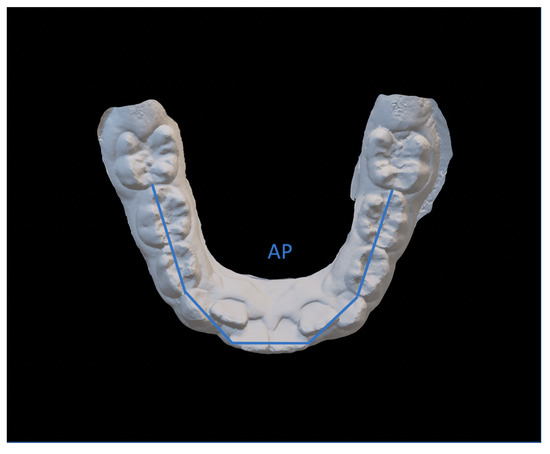

- Arch perimeter (AP), calculated as the sum of the distances between: mesial contact point of the first permanent molar; mesial contact point of the first bicuspid; mesial contact point of the first bicuspid; point of mesial lateral incisive contact; point of lateral mesial incisor contact; contralateral central incisor distal contact point.